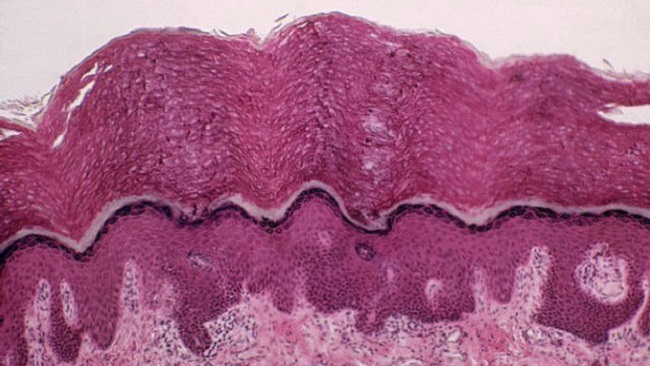

Previous to this fascinating revelation, our bodies according to science have only five major organs being the brain, heart, kidneys lungs and liver. The others that come next line are reproductive organs and of course the skin. The human body has 80 organs in total and now we may have 81.

Although the new organ may not be considered a part of the G5, it is nonetheless being considered a significant part of the human anatomy and also plays a big role in the functioning of it.

According to Scientists, the new organ will also reveal the process of how cancer spreads in the body which could lead to formulating of path-breaking medicine and treatment. The surprising thing about the new organ is that it was discovered by accident.